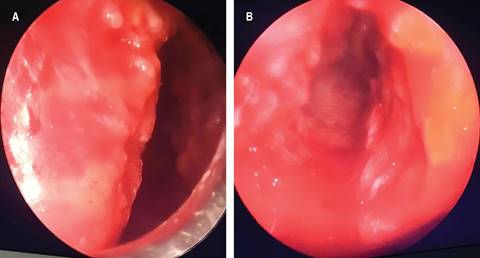

El paciente fue valorado por el Servicio de Cirugía de Tórax, que decidió realizar una resección endoscópica de la lesión traqueal. Durante el procedimiento, se evidenció estenosis traqueal a 2 cm de la tráquea, con una lesión dependiente de la pared lateral izquierda y anterior de la tráquea (Figura 2), de consistencia dura y calcificada, además de múltiples lesiones tipo empedrado. El procedimiento se realizó sin complicaciones.

Figura 2: A) Imagen de fibrobroncoscopia en la cual se identifica mucosa con lesión fibrótica dependiente de la pared lateral, de consistencia dura, localizada a 2 cm de las cuerdas vocales, que comprometía el 80% de la luz traqueal. B) Imagen de fibrobroncoscopia en la que se observa, distal a la lesión principal obstructiva, mucosa infiltrada e indurada, con múltiples lesiones nodulares de aspecto blanquecino que protruyen hacia la luz traqueal, respetando la pared posterior de la tráquea y dificultando el paso del broncoscopio.